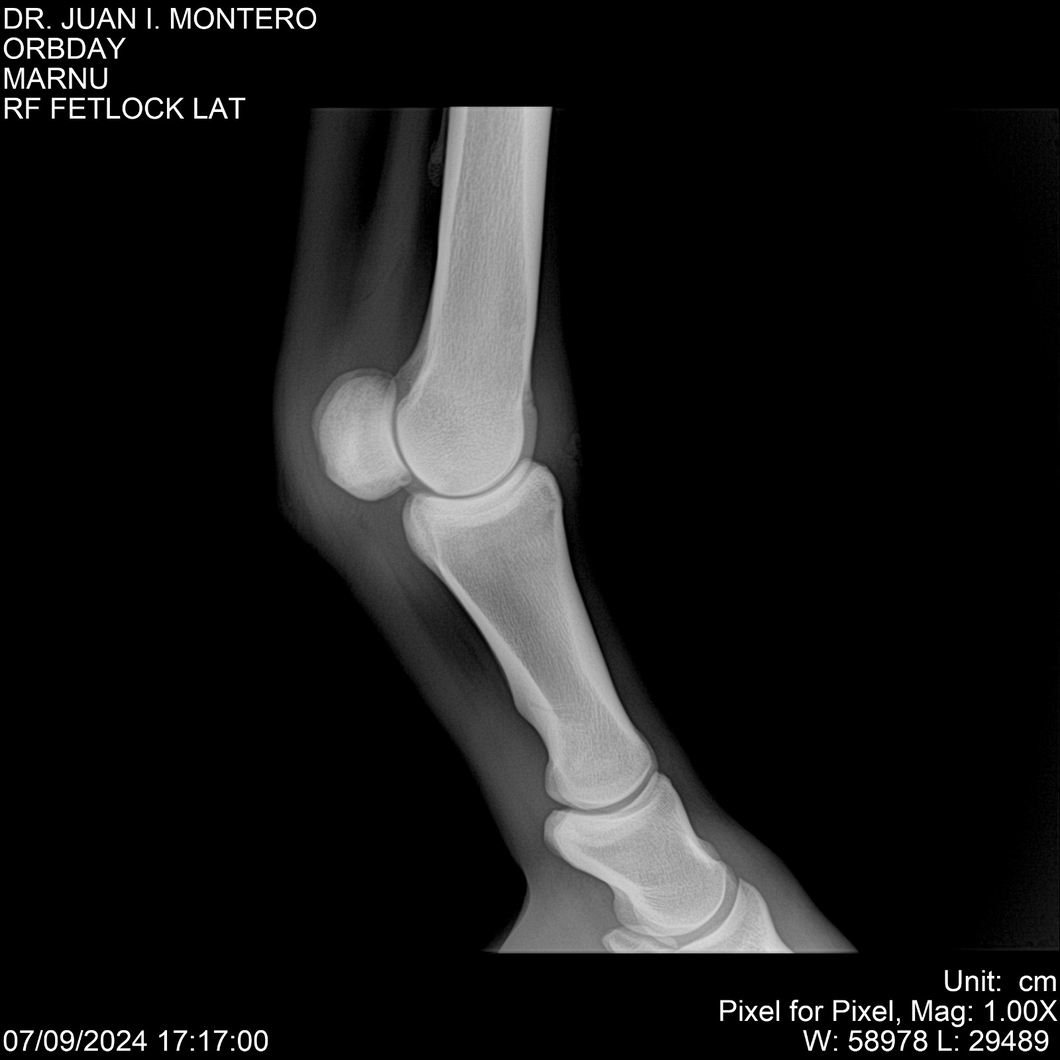

• Empresa: Abelenda N. R., Walter Hugo